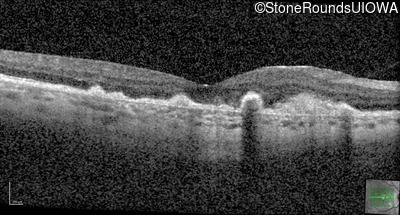

Malattia Leventinese (IIJ)

Malattia Leventinese (IIJ)

This 43 year old woman has experienced a gradual reduction in her central vision for the past 3 years.

| Malattia Leventinese | EFEMP1 | Arg345Trp CGG>TGG | AD |